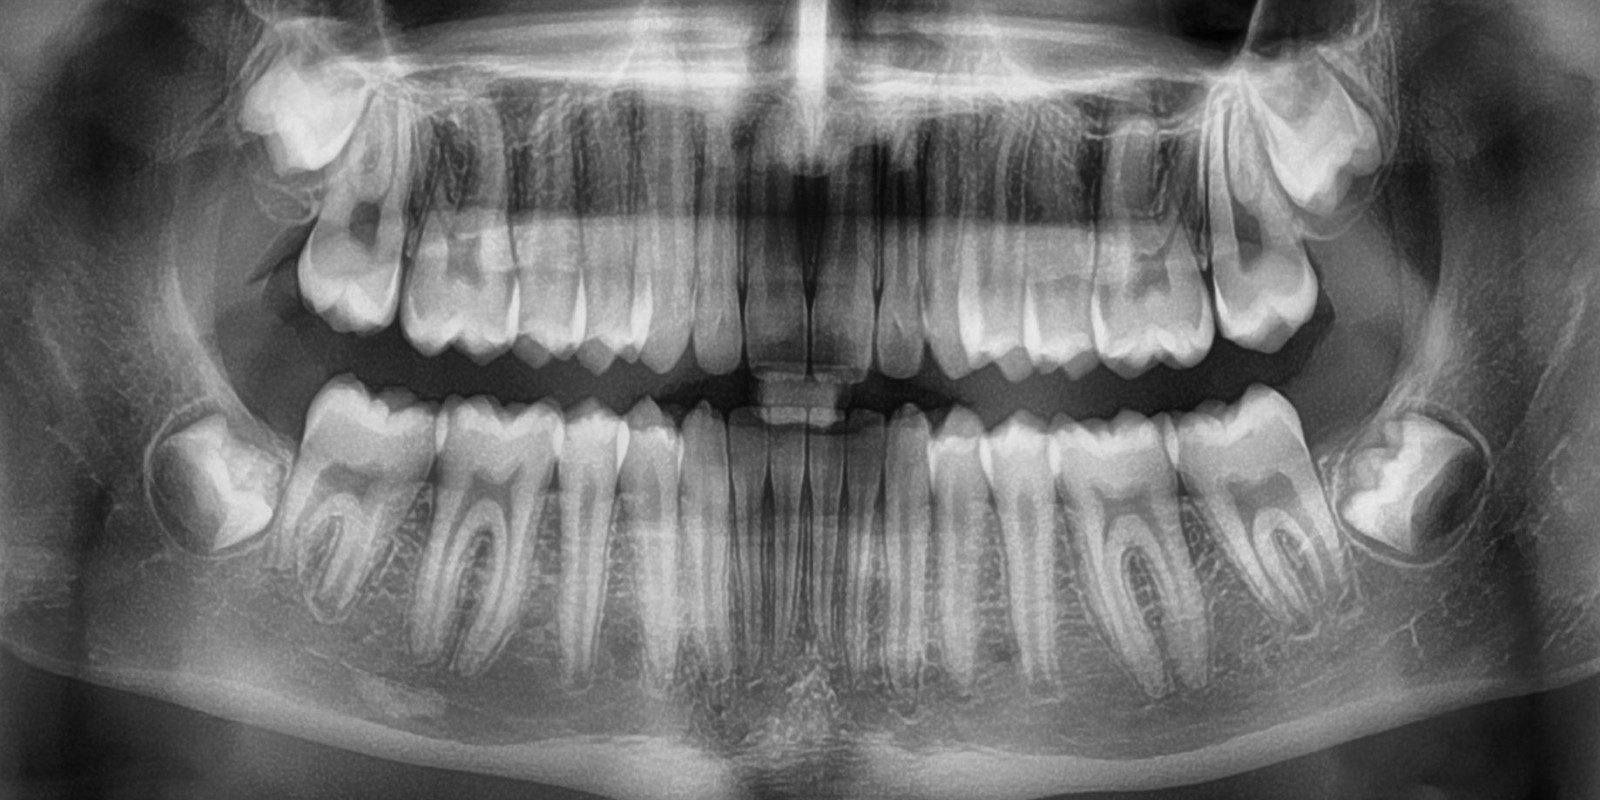

X-RAYS